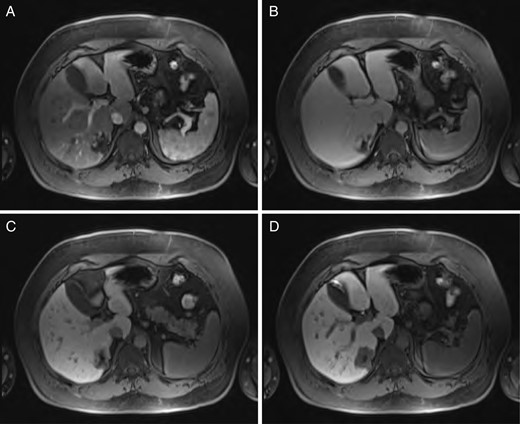

Sequential MRI imaging of hepatic hemangioma. Note delayed centripetal filling: (A) T1 arterial phase, (B) T1 60-s delay phase, (C) T1 postcontrast phase and (D) T1 hepatographic phase.

Hepatic hemangioma is a common hepatic incidentaloma that has characteristic features on both CT and MRI. Triple-phase imaging will reveal a hypoattenuating lesion on the early phase, while the delayed phases show peripheral isoattenuation (with the rest of the liver parenchyma) with a persistently hypoattenuating central portion that gradually fills [6]. This is due to the centripetally oriented vascular drainage of the lesion, flowing from the periphery toward the center.